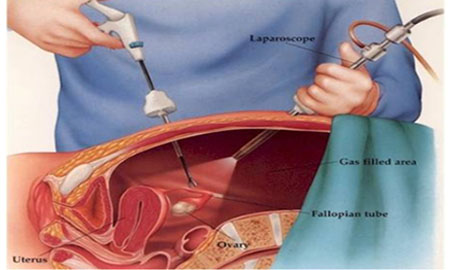

Iniya Hospital specializes in the treatment General Surgery. We have highly skilled personnel, the latest state of the art equipment, and convenient hours. We strive to satisfy every patient’s needs with comprehensive, sensitive, and cost effective care. Treating all kinds of General Surgery, Laparoscopy, General medicine, Neuro Medicine, Paediatric Medicine and Surgery, Surgical Oncology, Plastic Surgery, Urology, Orthopaedics, ENT and Dental, Skin , Physio- Theraphy. All neonatal and paediatric patients are also being treated here.. With you’ll receive the highly qualified care from our warm staff.